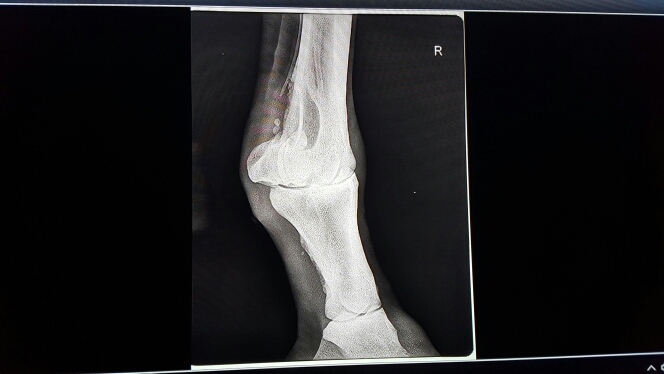

Помогите пожалуйста! Сделали рентгены, там в принципе и так видно что все плохо, но хотелось бы что бы кто-нибудь разъяснил что это и как можно помочь лошадке! Хотя бы снять боли! Так как вет внятно так и не объяснила что к чему. Заранее спасибо)

Нет, точного диагноза не поставили. Сказали только что кусочка кости не хватает, но это и так видно. Коваль наш сказал что скорее всего это сезамоидит.

Сесамоидит тоже, безусловно есть, но ИМХО он не главная проблема. Скорее всего проблема в кости, которая выше. Возможно там все еще идет лизис. Это весьма болезненный процесс.

Добавлю немного. Сесамовидная кость сильно деформирована. Не лечится. Еще мне кажется на снимке какие то мелкие обломки. Если это так, то они при движении травмируют ткани, а это больно. По идее можно устранить хирургически, но дорого и рискованно. Дырку в кости ну может быть где то за границей лечили бы операбельно, заполнив ее каким то составом. О подобных операциях я что то слышала, но в России таких вроде не делали и не делают. Учитывая жеребость, даже если у Вас есть огромные стредства на все смелые идеи и подобные эксперименты, год и даже больше ничего не сделать. К нагрузкам лошадь вряд ли сможет вернуться даже если найдутся супер опытные врачи.